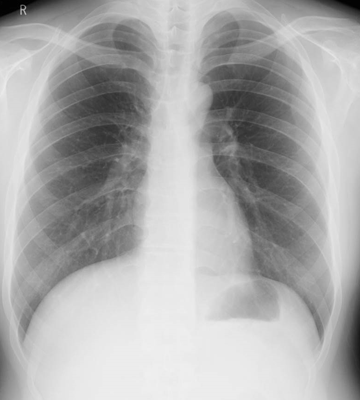

頚部の検査では、気管や頚椎(首の骨)、軟部組織(筋肉や皮膚などが写し出されている部分)など、胸部の検査では、肺、気管、気管支、心臓、血管、胸椎(背骨)、肋骨や軟部組織などが映し出されます。ただし、X線検査では上に書いた器官が重なって映し出されるので、細かい部分が十分に評価できません。このためさらに詳しく調べる必要がある場合はCTやMRI検査を行います。

胸部X線写真